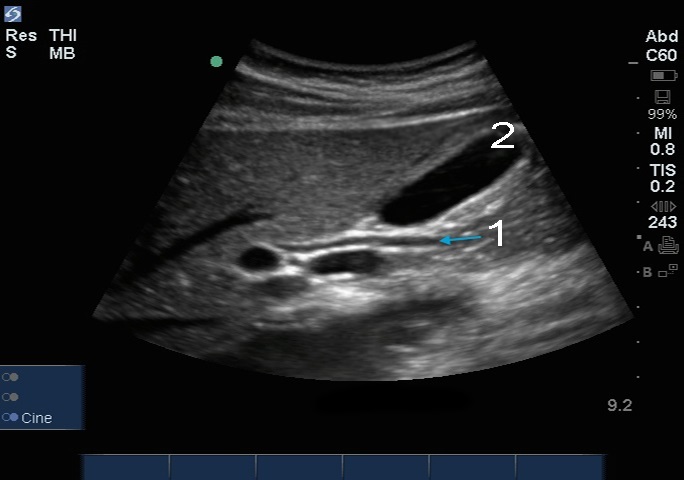

Bild: Gallenblase mit Ductus choledochus (DC)

Ductus choledochus (DC)

Gallenblase (GB)